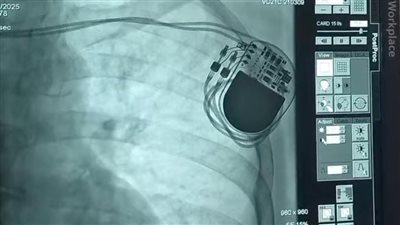

انقاذ حياة مسنة بتركيب منظم ضربات قلب دائم بالإسكندرية